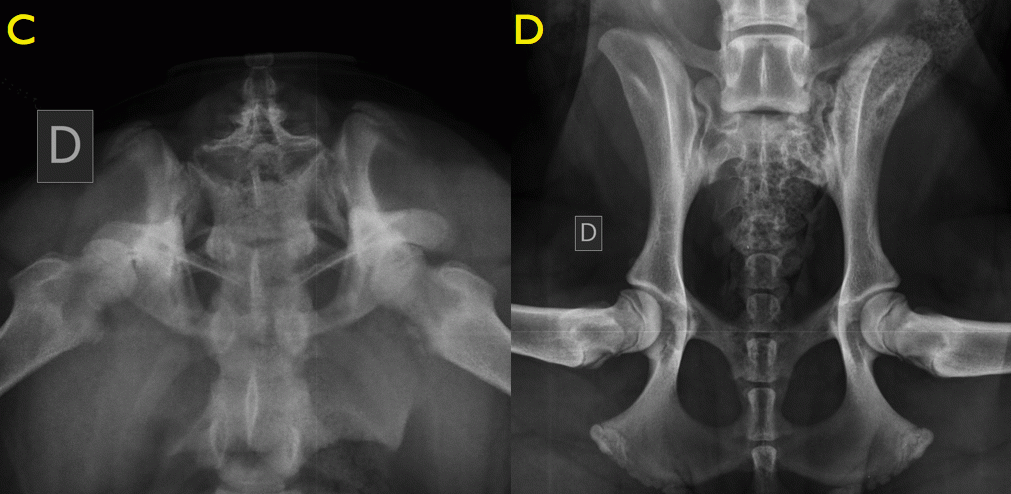

C) ventro-dorsale a rana D) DAR bordo acetabolare dorsale

Questa patologia non è diagnosticabile alla nascita poiché compare solo con lo sviluppo dell’articolazione. Durante la crescita del cucciolo, nei primi mesi di vita, può essere diagnosticata con uno studio radiografico del bacino in 4 proiezioni (diagnosi precoce a 4-5 mesi). L’esenzione da displasia dell’anca invece può essere accertata solo dopo il completamento dello sviluppo scheletrico mediante l’esecuzione di radiografie ufficiali. http://www.fsa-vet.it/

La diagnosi precoce di questa patologia può essere effettuata a tre e mezzo/ quattro mesi di vita, attraverso una visita ortopedica ed uno screening radiografico, in una fase in cui i sintomi clinici possono essere ancora assenti o “sfumati” (infatti una cane di 3 – 4 mesi di età spesso non manifesta dei sintomi clinici di displasia, anche se gravemente affetto, sia per il ridotto peso corporeo, sia per la capacità della cartilagine articolare di sopportare gli insulti iniziali).